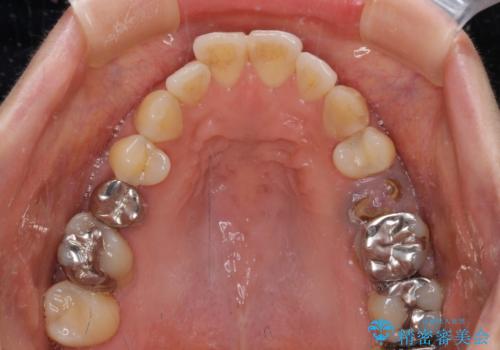

- 飛び出した上顎前歯と正中のズレを気にして来院された患者様です。

上顎正中が右側にずれていたので、むし歯が酷く抜歯が必要な左側臼歯を抜歯して正中を改善することとしました。

左下には新しいセラミックのブリッジが装着されていたため、ブリッジを壊さずに改善できるところまで咬み合わせを改善していくこととしました。

右上小臼歯は銀歯が装着されており、ワイヤー矯正の装置が装着できないため、事前に仮歯に変えてから矯正治療を行い、その後オールセラミッククラウンにて補綴治療を行いました。